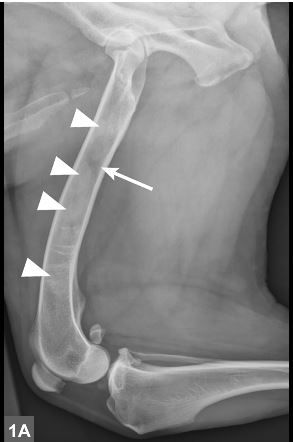

Panosteitis

Panosteitis affects large breed dogs "typically between 5 and 12 months of age." Clinical signs include lameness, usually in the ulna.

The article includes some cool xrays of this condition that typically resolves on its own. You can read more here. (Note: site requires free account creation.)